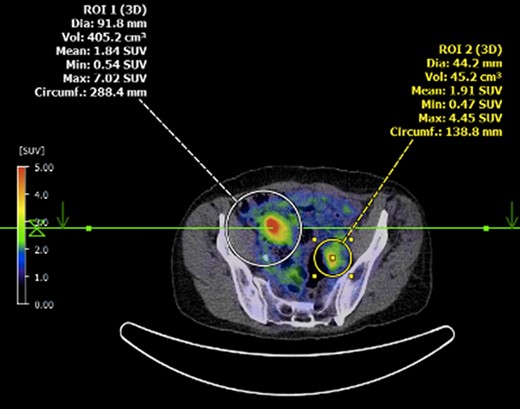

Submucosal biopsies from ascending colon unexpectedly demonstrated metastatic carcinoma consistent with female genital tract origin—CK7 positive; CK20 negative; PAX-8/WT-1/ER/CA125 all positive. A PET/CT was performed on the basis of the histological findings, which demonstrated intense FDG-avidity in the known site of disease in the ascending colon (Figs 2 and 3), as well as a separate focus of increased metabolism in the left pelvic side-wall (Fig. 4), which was presumed to represent an ovarian primary. There was no evidence of nodal or peritoneal disease, however, note was made of mild bilateral hydroureter without clear transition point. CA125 was 118 U/mL (Ref. range 0–35).

PET demonstrating intense metabolic uptake in thickened ascending colon.

Axial PET showing separate focus of avidity in left pelvic side-wall.